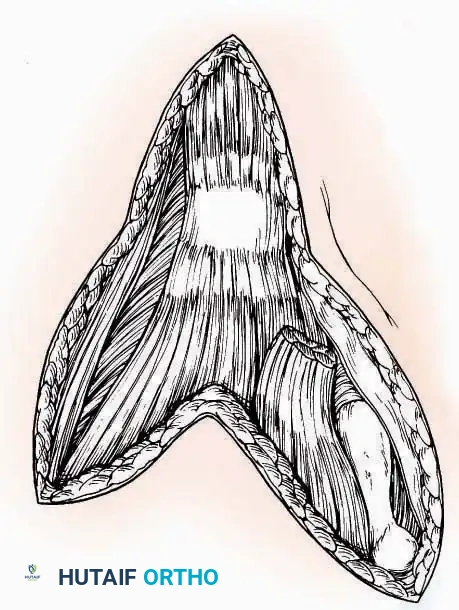

Indications: Extensive plantar fasciotomy, radical tumor resection, or complex osteomyelitis debridement requiring access to the entire plantar surface of the calcaneus.

Positioning: Prone, with the leg supported on a large sandbag.

Surgical Technique:

* Incision: Join the medial and lateral approaches described above to form a large, continuous U-shaped incision around the posterior four-fifths of the calcaneus.

* Flap Elevation: Deepen the incision directly to bone. Elevate a massive plantar flap consisting of skin, the specialized fatty heel pad, and the plantar fascia. Retract this flap distally to expose the entire plantar calcaneal tuberosity.